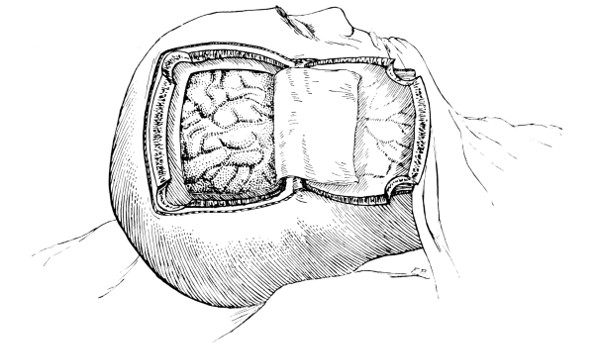

Fig. 18. Second Stage in the Formation of an Osteoplastic Flap. The bone-flap turned down and the dura mater exposed.

Fig. 19. Third Stage in the Formation of an Osteoplastic Flap. The dural flap turned down and the brain exposed. Note the relation of the scalp, bone, and dural incisions to one another.